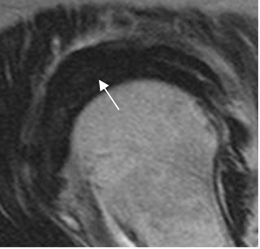

Fig 137. Tendinitis crónica reagudizada del supraespinoso.

A: RM coronal en T1 y B: RM coronal en STIR. Tendón engrosado por patología crónica. Muestra alteración de su señal, con hiperintensidad en STIR, por inflamación aguda.